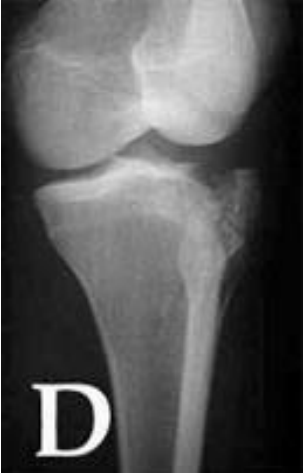

Observe a projeção radiográfica para fratura tibial superior, a seguir:

Disponível em:

https://www.scielo.br/scielo.php?script=sci_arttext&pid=S0102- 36162009000600002. Acesso em: 20 de agosto de 2021.

É CORRETO afirmar que é uma tomada em: